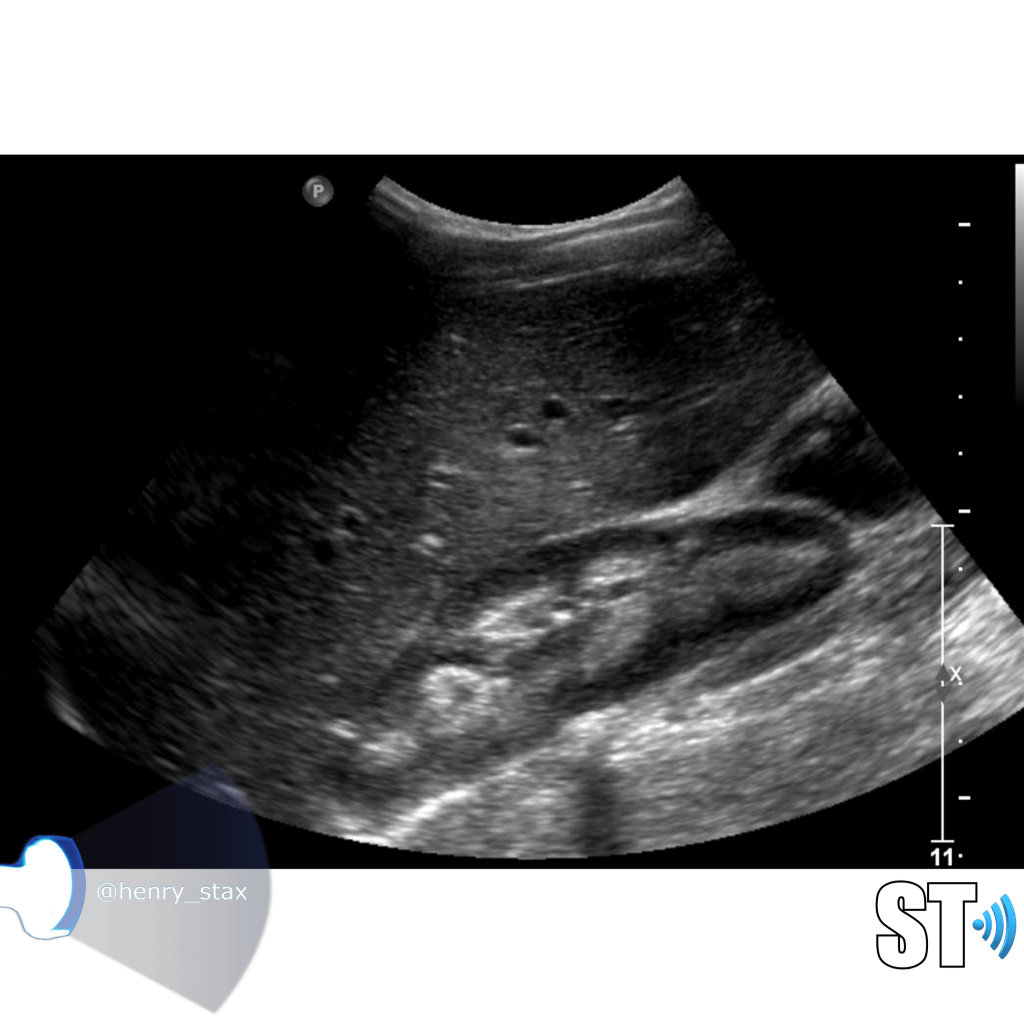

Renal Trauma

Renal trauma accounts for approximately 1-5% of all trauma admissions and as many as 10% of patients who sustain abdominal trauma. Injuries can range from contusions to life threatening injury. The types of trauma include penetrating (gsw, knife), blunt force (mva, sports injury), post procedure etc..

Patients may have abdominal/flank pain on the affected side, hematuria may also be present.